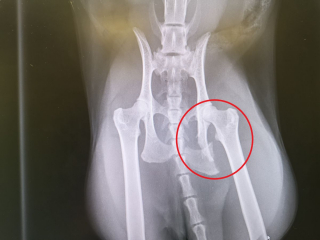

Heureusement, Billy a pu être rapidement pris en charge par les docteurs. Des antidouleurs lui ont été administrés, puis il a reçu une anesthésie générale afin de subir une radiographie.

Les résultats ont révélé une fracture du bassin, en plus d’une plaie importante au niveau de la patte.

“Les blessures de Billy correspondaient à un accident de la route” a expliqué le vétérinaire. “Il avait besoin de soulagement de la douleur et de soins 24 heures sur 24, il a donc été hospitalisé pendant trois autres nuits”.